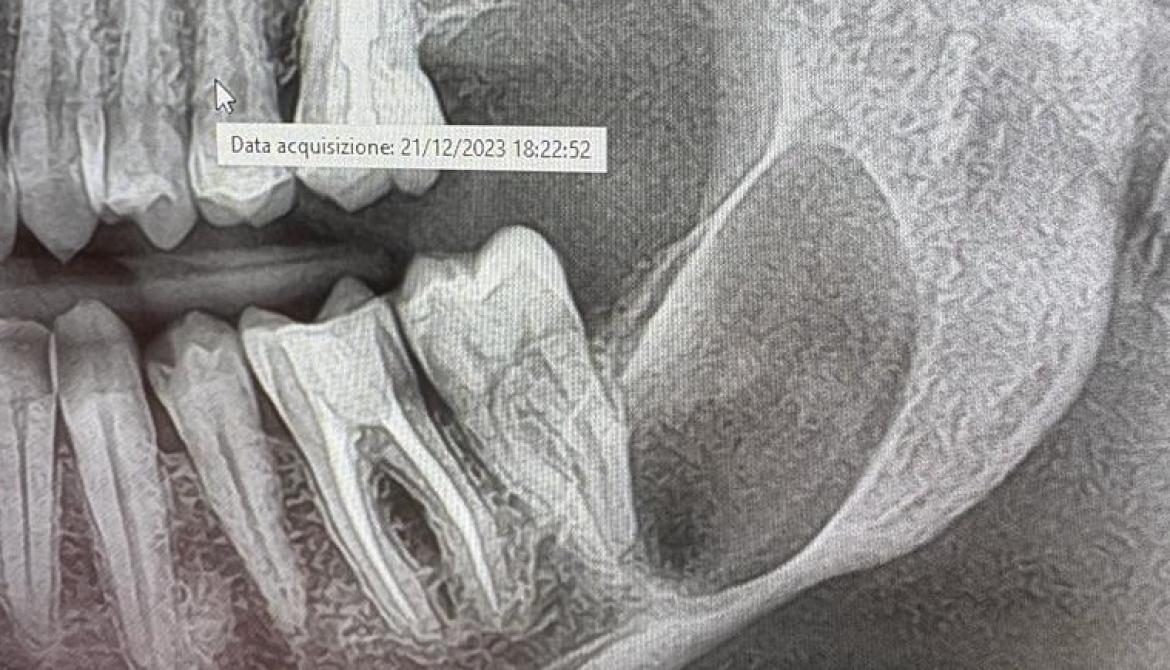

Asportazioni lesioni cistiche dei mascellari

Le lesioni cistiche delle ossa mascellari sono delle cavità patologiche che si formano all'interno dell'osso mandibolare o mascellare, spesso in relazione a un dente. Possono essere di diverso tipo, come cisti follicolari, cheratocisti, cisti aneurismatiche, cisti ossee solitarie, ecc.

La diagnosi si basa su esami clinici, radiografici e istologici, che permettono di differenziare le cisti da altre lesioni osteolitiche e di stabilire il tipo e la gravità della cisti.

Il trattamento delle lesioni cistiche dei mascellari è sempre chirurgico, tranne che nel caso delle cisti radicolari che, in alcuni casi, possono regredire dopo trattamento endodontico. La chirurgia consiste nell'asportazione della cisti e del suo rivestimento epiteliale, con eventuale ricostruzione ossea se necessaria. Il materiale asportato va sempre inviato per esame istologico per confermare la diagnosi e valutare il rischio di recidiva.